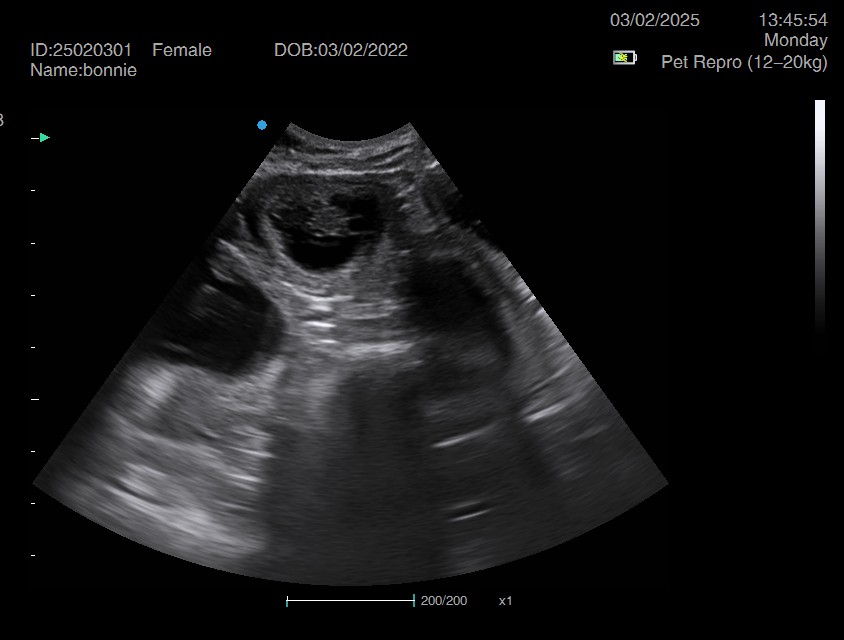

Ultrasound pregnancy scanning is a safe, non-invasive way to confirm pregnancy in dogs and cats, offering breeders and pet owners peace of mind and vital information to support responsible care. It allows us to detect gestational sacs, assess foetal development, and estimate litter size—all while ensuring the wellbeing of the animal.

Pregnancy can sometimes be detected as early as Day 18 post-mating, but scanning at this stage is not routinely recommended. Embryos are still developing and may not be clearly visible, and there is a natural risk of embryo resorption, which can lead to misleading or inconclusive results.

For the most accurate and reliable scan, we advise booking between Day 25 and Day 32, when pregnancy is more easily confirmed and foetal structures are clearer. If an early scan is performed and no pregnancy is detected, we offer a FREE complimentary re-scan after 7 days at the clinic to ensure clarity and support informed decision-making.

Our approach balances early insight with ethical care—always prioritizing the comfort of the animal and the accuracy of the results.